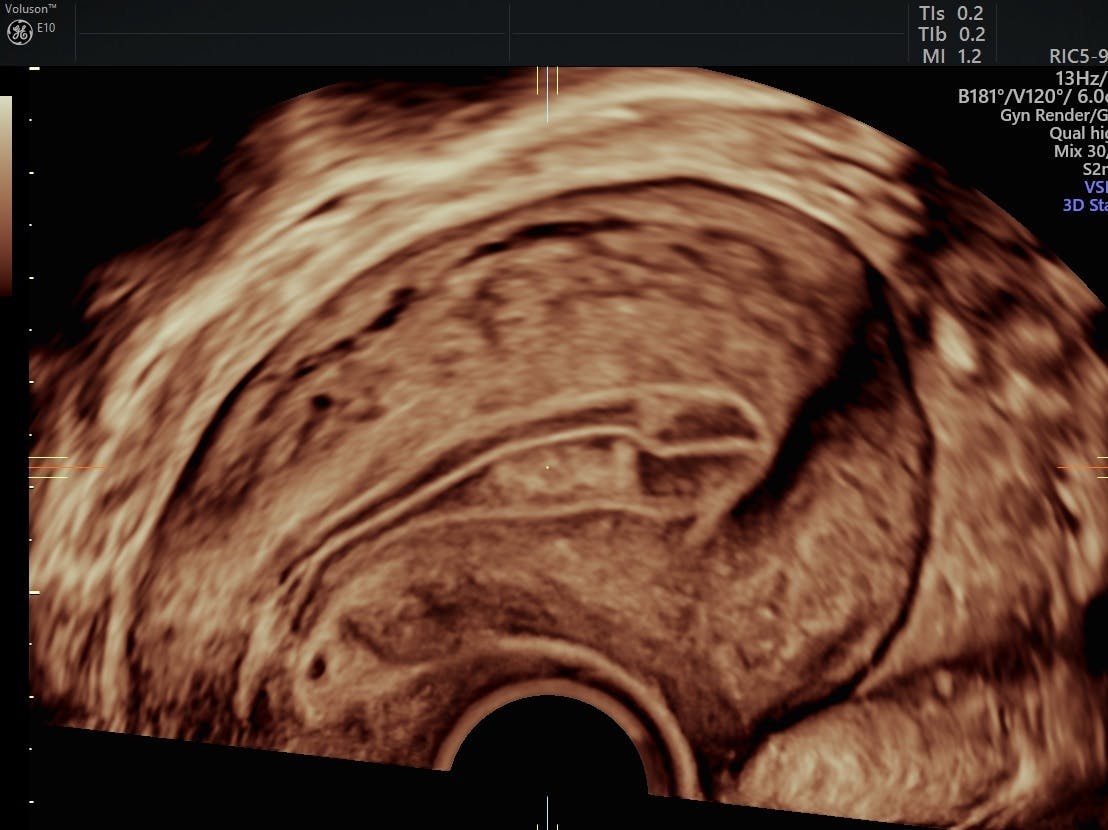

Postmenopausal Bleeding | Dr N Layyous from www.layyous.com Postmenopausal bleeding is vaginal bleeding that happens at least 12 months after your periods have stopped. Post menopausal bleeding, benign and malignant causes of post menopausal bleeding and. The endometrium is the tissue that lines your uterus. However, postmenopausal bleeding could result from something serious, so it's important to see your doctor. While there is a link between bleeding and cancer in the uterine lining (endometrial cancer), in 90% of postmenopausal women when bleeding occurs, it's. At both i talked to the nurses. Post menopausal bleeding can occur for a number of reasons, the most common of which is hormone replacement therapy. Bleeding after menopause is mostly referred as postmenopausal bleeding or pmb.

There are many different reasons for postmenopausal bleeding vaginal bleeding after menopause is one of the first symptoms of certain types of cancer. Postmenopausal vaginal bleeding can be caused by: Although bleeding after menopause is not always cause for concern, a woman should always consult her doctor if she does have postmenopausal bleeding to rule out more serious causes, such as endometrial cancer. Mr angus mcindoe, a top gynaecologist, explains how it is diagnosed. Learn how postmenopausal bleeding (pmb) is defined for practical purposes. In this procedure, the uterus, cervix and ovaries. Menopause symptoms include hot flashes, night sweats, abnormal vaginal bleeding, vaginal itching, dryness, and pain, urinary symptoms, weight gain, acne, skin texture changes, and mood what are the signs and symptoms of menopause? The tissue that lines the uterus can become very thin after menopause. Postmenopausal bleeding is any bleeding, or even a brown discharge, after the menopause. Postmenopausal bleeding is a common symptom of endometrial cancer, but it also can be caused by cervical and vulvar cancer. Whether it is breast cancer or prostate cancer. Breast cancer is not contagious; Post menopausal bleeding, benign and malignant causes of post menopausal bleeding and.